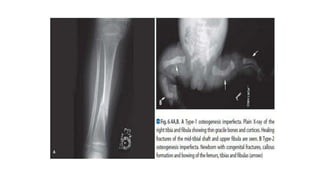

This document discusses a disease and its investigation and management. It begins by introducing Dr. Aniket Wankhede from MGIMS Sevagram and asks what the disease is. It then asks how the disease happens and discusses its causes. Next it asks how the disease appears on x-rays and describes symptoms some people experience living with it. Finally, it asks how the disease will be investigated and managed.